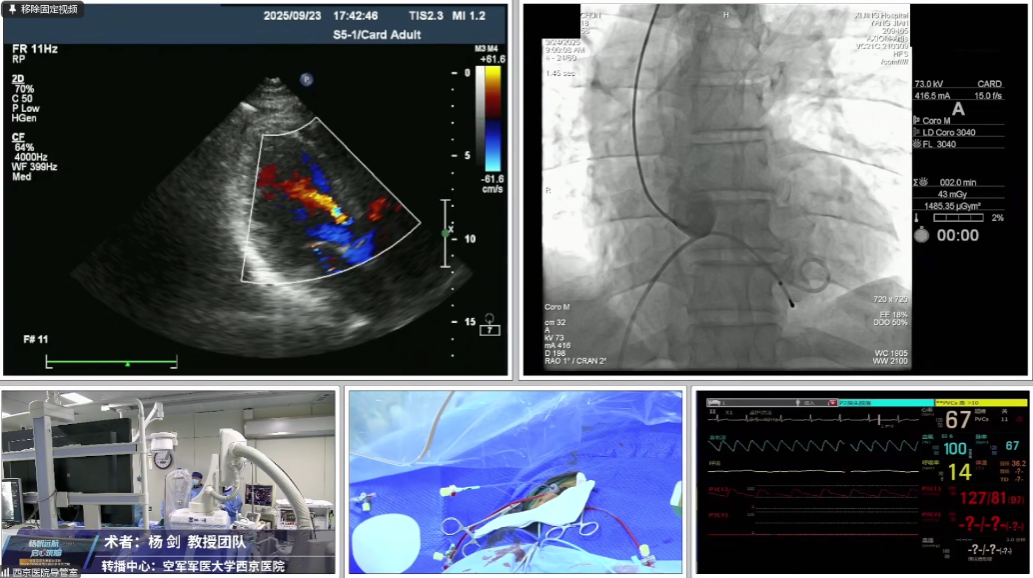

手术直播是验证理论与锤炼技术的核心环节。杨剑教授团队通过直播演示了三台教学价值极高的TAVR手术,涵盖单纯主动脉瓣反流、极重度钙化Type 1二叶瓣与超大左房合并二尖瓣狭窄,系统展示了应对不同解剖难点的手术策略与技巧。

手术直播1:单纯主动脉瓣反流

本例患者66岁男性,间歇性胸闷、气短1年。超声提示中量主动脉瓣关闭不全,合并少量二尖瓣与三尖瓣反流。

CT评估提示三叶瓣结构,无明显钙化,窦部空间充足;冠脉开口位置安全;主动脉弓角度锐,外周血管走行迂曲,术中释放轴向控制存在挑战。

手术中经右股动脉入路,拟植入VenusA-L 29mm瓣膜。因弓部角度锐利,导丝跨弓两次尝试后成功,造影未见主动脉夹层。最终在超声引导下回收重置,瓣膜同轴性理想,展开良好,反流完全消失,手术顺利完成。

瓣膜过弓

瓣膜释放

超声引导确认植入深度

回收后再次释放, 瓣膜植入同轴性良好,展开充分,反流消失, 手术顺利完成